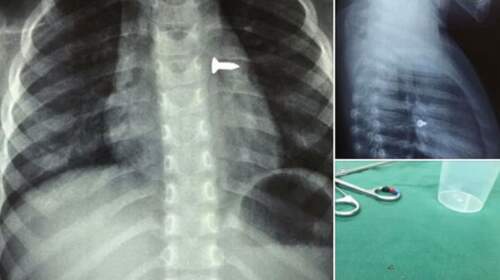

Read MoreΗράκλειο: 3χρονο κοριτσάκι κατάπιε βίδα – Από τον πνεύμονά της την έβγαλαν οι γιατροί

Σε μία μεγάλη περιπέτεια μπήκε χθες μία οικογένεια στο Ηράκλειο. Σύμφωνα με τις πληροφορίες που γνωστοποίησε μέσω ανάρτησής του ο αναπληρωτής καθηγητής ΩΡΛ της Ιατρικής Σχολής Κρήτης, κ. Μανώλης Προκοπάκης, ένα κοριτσάκι τριών ετών εχθές μεταφέρθηκε εσπευσμένα σε νοσοκομείο του Ηρακλείου, καθώς είχε καταπιεί μία βίδα. Αμέσως υποβλήθηκε σε ακτινογραφίες που φανέρωσαν πόσο επικίνδυνη ήταν η κατάστασή του, καθώς η…